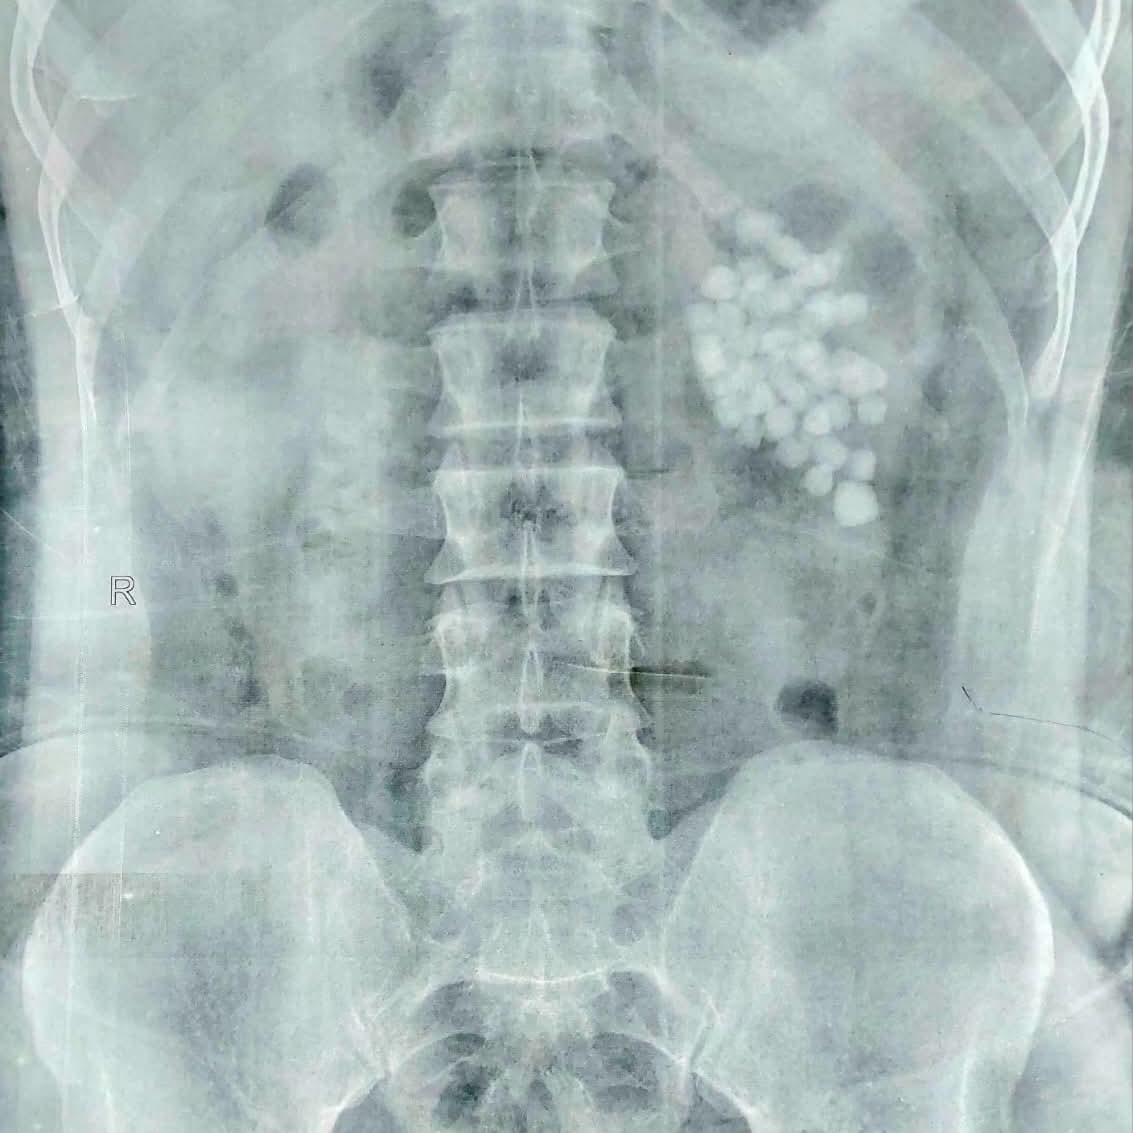

نجح فريق طبي متخصص ، بمستشفى المعبر الجامعي بقنا ، في إجراء عملية دقيقة لاستخراج 58 حصوة من الكلية اليسرى لمريض يبلغ من العمر 40 عامًا، وذلك باستخدام أحدث تقنيات مناظير الكلى المتقدمة.

وأوضح الدكتور مصطفى عبد الرازق ، رئيس قسم المسالك البولية، أن المريض وصل وهو يعاني من آلام متكررة وارتفاع في نسبة الأملاح، وبفحصه تبيّن وجود عدد كبير من الحصوات المتجمعة في حوض الكلية اليسرى، ما استدعى التدخل الجراحي حفاظًا على وظائف الكلية.